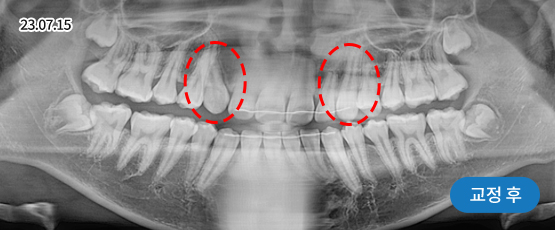

매복치 Solution

매복치는 잇몸 속에서 인접 치아에 손상을 줄 수 있어

치아 견인을 통해 제자리를 찾아주어야 정상적으로 치아가 자리 잡을 수 있습니다.

* 치근흡수, 잇몸퇴축 등 부작용이 발생할 수 있습니다.